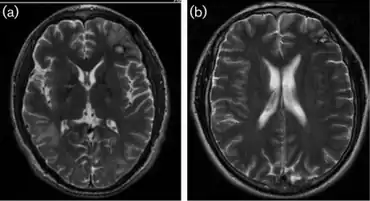

a)MRI- oedema from mass in right temporal b) MRI- two years afterword conclusion of the CNS lesions